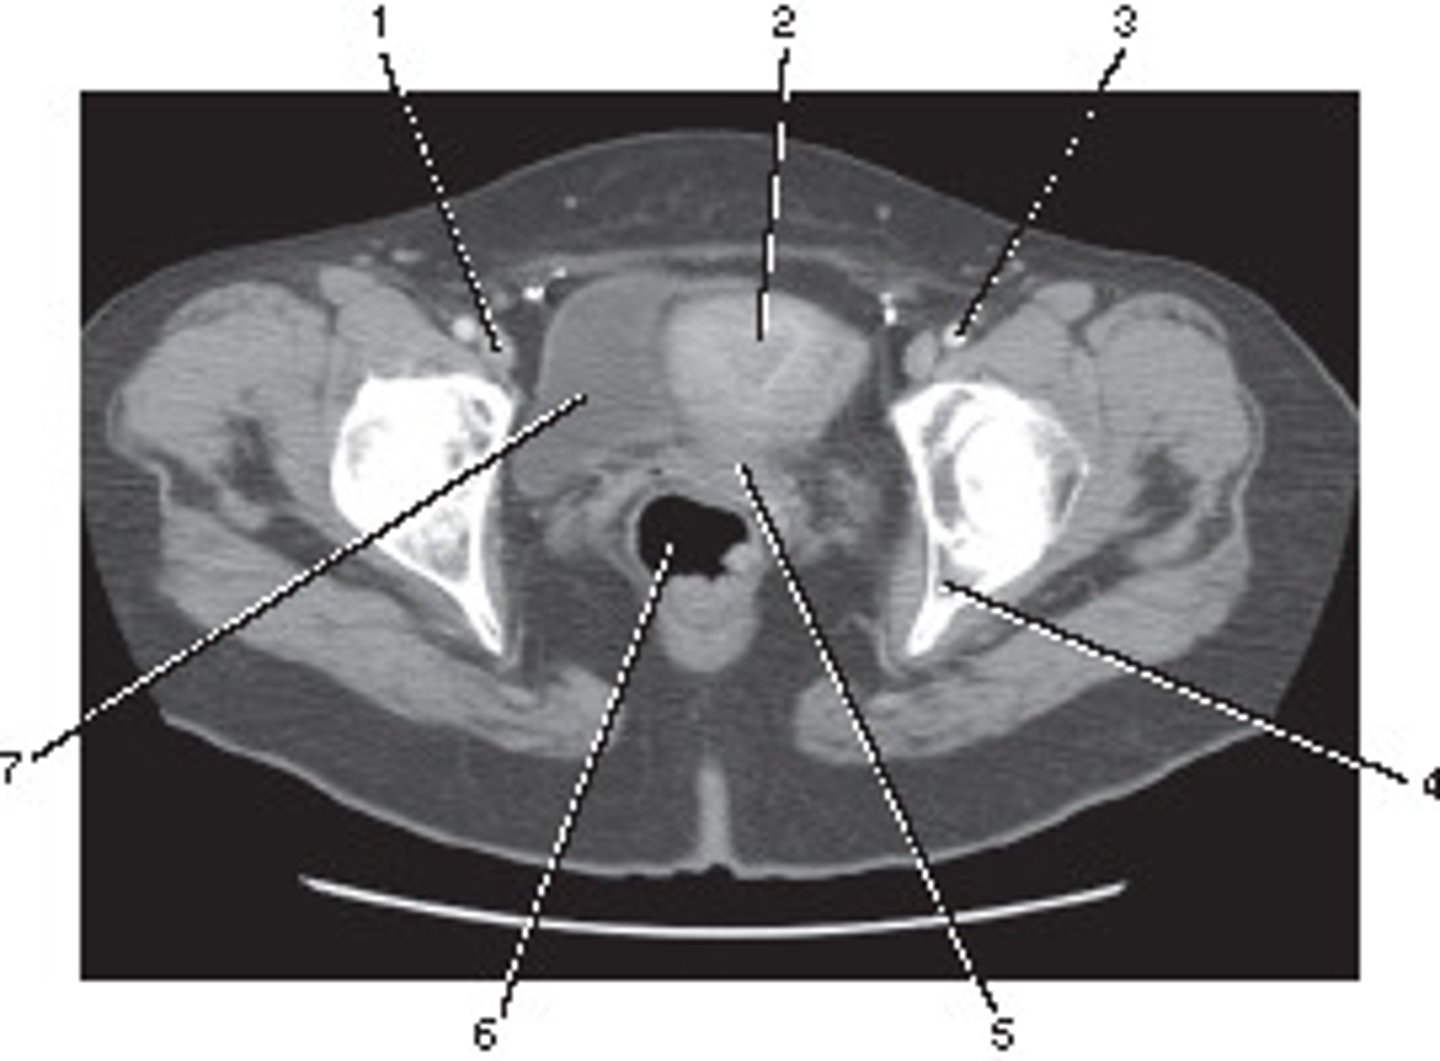

Ileum

Number 1 corresponds to which of the following?

<p>Number 1 corresponds to which of the following?</p>

Uterus

Number 4 corresponds to which of the following?

<p>Number 4 corresponds to which of the following?</p>

Ilium

Coccyx

Femoral Artery

Ovarian Cyst

This ROI has a HU value of +10, given its position in a female bony pelvis, this most likely represents:

<p>This ROI has a HU value of +10, given its position in a female bony pelvis, this most likely represents:</p>

External Iliac Vein

Number 2 corresponds to which of the following?

<p>Number 2 corresponds to which of the following?</p>